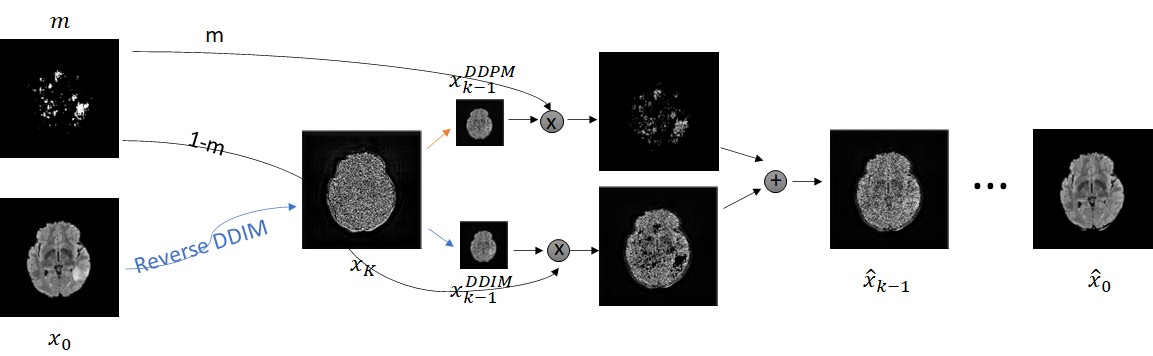

In order to do so, we exploit the saliency maps obtained with ACAT to guide the image generation process of diffusion models. We first train a Denoising Diffusion Probabilistic Model (DDPM) (Ho et al., 2020) on healthy samples and use a combination of DDPM and Denoising Diffusion Implicit Model (DDIM) (Song et al., 2020) sampling to remove pathological areas from the images. In particular, we first map an abnormal image to its noised version by using the reversed sampling approach of DDIMs. Then, with DDPM sampling we modify the pathological area, identified by the saliency map obtained previously, to recover the normal structure, based on the surrounding anatomical context. The parts of the image without pathological elements are mapped back to their original appearance with DDIM sampling. We fuse these two components at each step of the sampling process, so that the final resulting image has a realistic appearance, with a smooth transition between edited and unedited parts. We refer to our method as Dif-fuse.

In our work, we aim to tackle this challenge by proposing a two-step approach. First, we employ ACAT to obtain initial saliency maps, which provide a rough identification of the regions requiring modification. Then, we introduce a novel sampling technique from diffusion models that enables targeted modifications to these regions while preserving the remainder of the image unchanged. By fusing both components at each timestep, we achieve a seamless transition between the edited and unedited parts, resulting in a realistic output. By considering the difference between the counterfactual example and the original image, we can also obtain the final anomaly map.

We observe that our sampling approach not only generates highly realistic counterfactuals but also enhances the initial saliency maps obtained in the first step using ACAT. This is possible because the selected regions may not undergo complete modification by the diffusion model, allowing for the preservation of healthy anatomical features identified in the initial attribution maps. A visual representation of our approach is presented in Figure 1.

3.2 Dif-fuse

In our approach, we employ a DDPM trained on healthy samples and saliency maps obtained from adversarially generated counterfactual examples as in ACAT (Fontanella et al., 2023). We chose ACAT as it showed superior performance in the identification of pathological areas in brain and lung CT scans. However, in principle, saliency maps may also be generated with any other approach. Given a diseased image , we first select a noise amount and map the image to its noised version with the inverse DDIM sampling scheme proposed in (Song et al., 2020):

We then smooth the saliency map with a Gaussian kernel of size to obtain a mask . We edit the diseased regions inside the mask with DDPM sampling. Since the diffusion model was trained on normal samples, these regions are mapped to a healthy appearance. The rest of the anatomy needs to be preserved and therefore we employ DDIM sampling for the areas outside of the mask, as in Eq. (7), with . In order to obtain a coherent result, we mix the masked part with the rest of the image at each sampling step. In other words, given , we compute:

| (9) |

where is the Hadamard product. In this way, the editing process is focused on the parts that were captured by the saliency map, preventing random changes to the structural characteristics of the scan. In fact, the DDIM sampling guarantees reconstruction of the parts that don’t need to be edited. Moreover, changes to the pathological parts are performed by the DDPM considering the surrounding anatomical context. Our method is summarised in Algorithm 1.

When computing with Eq. (9), the sum of the two components may not produce a perfectly coherent result. However, the incoherence is resolved by the next diffusion step, which fuses the two components better. This would not be the case if we simply computed with DDPM and then applied the mask only at the end of the sampling process. An illustration of this effect is presented in Figure 3, where we can observe how the normal image, generated by applying the mask solely at the conclusion of the sampling process (b), exhibits some artifacts and lacks a seamless transition between the edited and unedited regions.